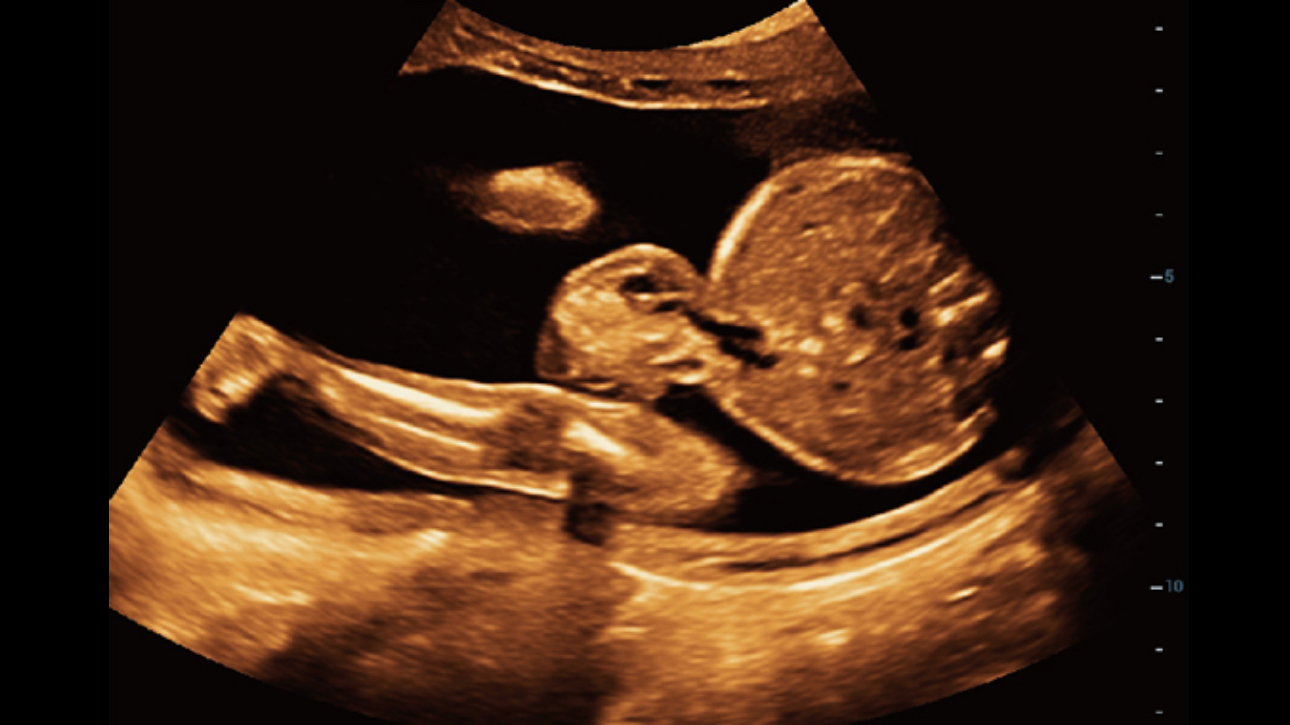

Mindray’s exclusive pioneering technology positions the Resona 6 as the industry’s first ultrasound system to allow fully automatic and accurate detection of the most significant planes and frequently used measurements of fetal CNS, leading to intelligent diagnosis, improved throughput, and reduced user dependency.

Smart Planes CNS provides a user-friendly tool that greatly improves scanning efficiency through increased accuracy coupled with automated operation. With a simple button click on a 3D fetal brain volume image, the standard CNS scanning planes (MSP, TCP, TTP and TVP) and a range of related anatomical measurements (BPD, HC, OFD, TCD, CM and LVW) are obtained immediately.

Acquiring an optimal view of the fetal face in 3DUS is cumbersome and time-consuming. In some cases, it is impossible to get rid of the occlusions such as cord, placenta, uterus, and extremities. The new Resona 6 with Zone Intelligence provides a fast and intelligent optimization for fetal face with simple one-touch operation. It can immediately remove occlusions in the volume data and eliminate unwanted noise information, and generate an optimal view of the fetal face with minimized effort.